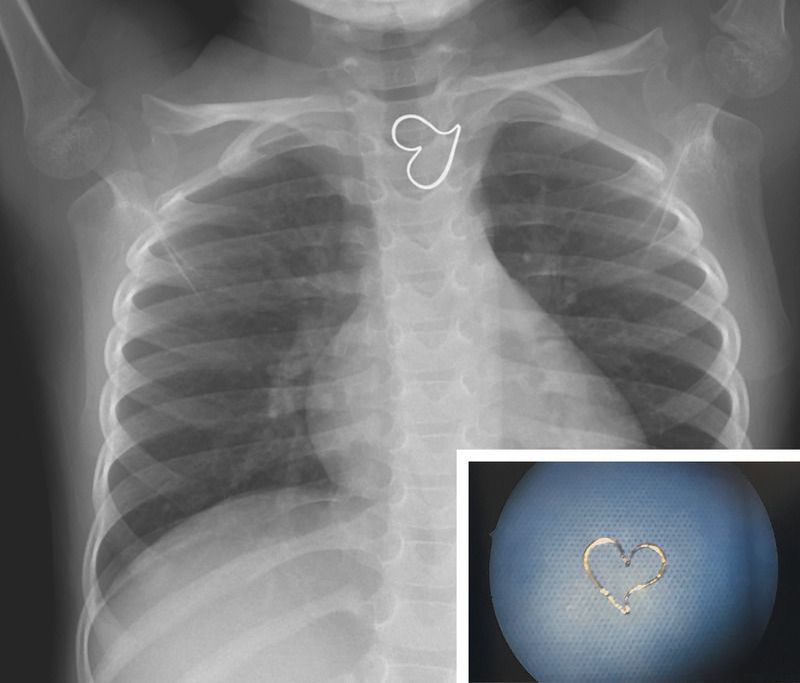

A 3-year-old girl presented to the emergency department after she had ingested a metal pendant. She had not vomited and had no pain in her chest. A physical examination was unremarkable. A radiograph of the chest confirmed a heart-shaped foreign body in the proximal thoracic esophagus. Ingestions of foreign bodies are most commonly reported in children 1 to 3 years of age. Ingested items that warrant immediate endoscopic removal from the esophagus include sharp objects, button batteries, and foreign bodies that have been present for longer than 24 hours. Asymptomatic children who have ingested items that do not have potentially dangerous features may be observed without intervention to allow the foreign body to pass spontaneously. In this patient, the position of the foreign body appeared to be unchanged on repeat radiographs of the chest. The patient was taken to the operating room to undergo rigid endoscopy, and a gold heart-shaped pendant was removed (inset). Reinspection of the esophagus showed minor abrasions of the esophageal mucosa. After the procedure, the patient recovered well and was discharged home.